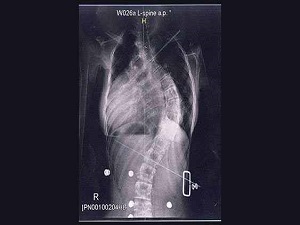

Zaman içerisinde omurga eğriliğinin kambur duruşa ve akciğer kapasitesinin azalmasına yol açtığına dikkat çeken Yrd. Doç. Dr. Burcu Önal, “Geleceğini şekillendirmeye çalıştığınız çocuğunuzun nefesini okul çantaları kesebiliyor ve vücut şeklini bozabiliyor.” diyor. Her yüz gençten üçünün omurgasında eğrilik oluğunu vurgulayan Fatih Üniversitesi Tıp Fakültesi Hastanesi Fizik Tedavi ve Rehabilitasyon Uzmanı Yrd. Doç. Dr. Burcu Önal, çocukların çantayı tek omuzda taşımasının omurga eğriliklerine neden olduğunu belirtiyor. Çantaların ağır olması durumunda çocukların öne doğru eğilmeye başladığını belirten Önal, “Bu durum ileriki yıllarda duruş bozukluğu oluşturmaktadır. Çocukların dengelerini bozup düşmelerine sebep olmakta, sırt ve bel ağrısı bacak kaslarında gerginliği artırarak ağrı oluşmasına sebep olmaktadır.” diyor. Önal, “Çocukların omuz askısının normalden daha fazla omuz bölgesine baskı yapması dolaşım bozukluğuna sebep olmakta, ağrı oluşumunu artırmaktadır. Duruşun dik olması akciğerin rahat çalışmasını sağlarken, omurgada oluşan eğrilik, akciğer kapasitesinin azalmasına nefes almakta zorlanmaya sebep oluyor.” şeklinde konuşuyor. “Hafif olarak nitelendirdiğimiz bir ağırlık bile omurganın duruşunu değiştirebiliyor.” diyen Önal, henüz gelişim dönemindeyken sürekli bir ağırlık altında kalan çocuklarda ileriki dönemlerde kronik bel ve sırt ağrıları oluşabileceğini aktarıyor.